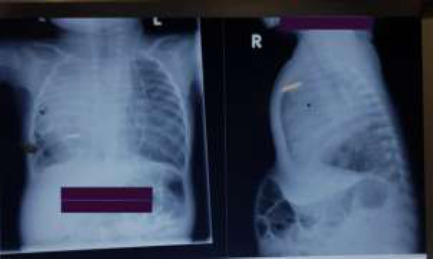

Scimitar syndrome in a four-month-old infant.

The Scimitar syndrome or pulmonary venolobar syndrome is a rare, complex and variable congenital anomaly of cardiopulmonary development characterised by an abnormal right-sided pulmonary venous drainage in the inferior vena cava, malformation of the right lung, abnormal arterial supply and sometimes cardiac malformations. These serious anomalies notwithstanding, their presentation is varied, ranging from asymptomatic to severe symptoms, particularly in the neonatal and early infantile period. Some symptomatic cases are misdiagnosed as recurrent lower respiratory tract infections or as heart failure, missing the underlying congenital anomaly. Considering associated serious complications such as pulmonary hypertension and a high mortality rate, accurate and timely diagnosis is mandatory. This requires a high index of suspicion, not only by clinicians but also by radiologists who encounter suggestive chest radiographs in asymptomatic children. Still, the classic radiological finding for which the condition is named is seen in only about 50% of all cases and only 10% in affected infants. We highlight this case to heighten clinicians' and radiologists' suspicions about Scimitar syndrome.